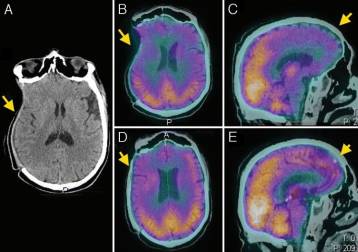

结果显示,颅骨成形术前,9例(26.5%)患者的GOS评分为5分,25例(73.5%)GOS评分为4分;颅骨成形术后,34例(100%)患者GOS评分为5分,较术前提高。各项认知测试结果表明,35.3%-90.9%的患者于颅骨成形术后认知功能改善(表1)。此外,94%患者的脑SPECT成像结果提示,在不同脑叶中脑灌注情况均得到改善(图1-4)。

图3. A.颅脑CT显示右侧颅骨缺损;B、C.颅脑SPECT示术前枕叶脑血流灌注低;D、E.颅脑SPECT示术后枕叶脑血流灌注较术前改善。